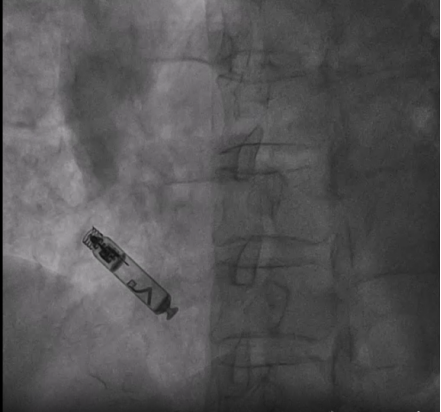

无导线起搏器体积仅胶囊大小(约 1.0cc),重量不足 2 克,通过导管直接植入心腔,无需切开皮肤或植入传统的电极导线,刚好解决了解剖变异问题。术中使用 Aveir AR 专用输送系统经右侧股静脉-下腔静脉血管途径顺利将起搏器送入右心房,并精准释放于右心耳,测试参数满意,术后心电监测记录到患者再次出现心脏停搏,起搏器及时启动帮助跳动,患者未发生不适症状。术后 24 小时程控起搏器阈值良好,工作状态无异常。患者头晕、心慌症状显著缓解,无需换药拆线,第三日即办理出院,如此效率,让患者及家属连连称赞。